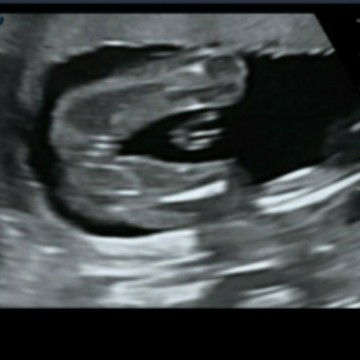

Girl or boy?

kalau camni confirm girl ke ehh? kalau betul Alhamdulillah . pape pun sy xkesah yg penting bby sihat sempurna je ☺

mcm girl. berapa week scan sis?

Girl